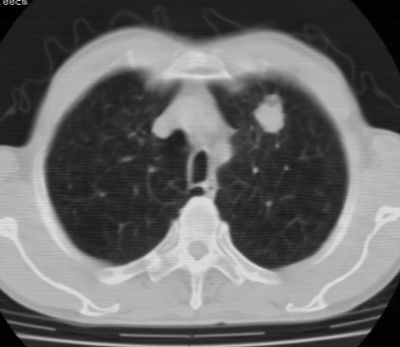

标题: CT24783:m71,既往肺心病史3年,现咳嗽,憋喘。 [打印本页]

标题: CT24783:m71,既往肺心病史3年,现咳嗽,憋喘。

1、左肺上叶spn,毛刺+分叶+血管集束征,考虑周围型肺癌可能性大

2、全小叶性肺气肿。

1)左肺上叶周围型肺癌可能。2)两肺全小叶型肺气肿。

左上周围型肺癌,全小叶型肺气肿。